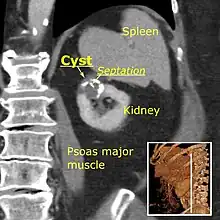

Bosniak II cyst at the lower pole of right kidney with septations within.

- Benign cyst with a few thin septa, which may contain fine calcifications or a small segment of mildly thickened calcification. This includes homogenous, high-attenuation (60–70 Hounsfield units[3]) lesions less than 3 cm with sharp margins but without enhancement. Hyperdense cysts must be exophytic with at least 75 percent of its wall outside the kidney to allow for appropriate assessment of margins, otherwise they are categorized as IIF.[6]

The complex cyst can be further evaluated with doppler ultrasonography, and for Bosniak classification and follow-up of complex cysts, either contrast-enhanced ultrasound (CEUS) or contrast CT is used.[12]